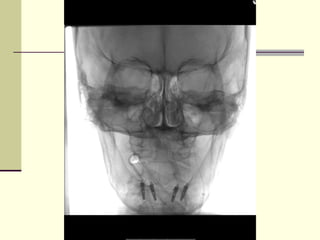

‫מתי מטפלים?‬

‫באדיבות ד"ר‬

‫בקון‬

‫יחידת הנוירו-‬

‫אינטרבנשיונל‬